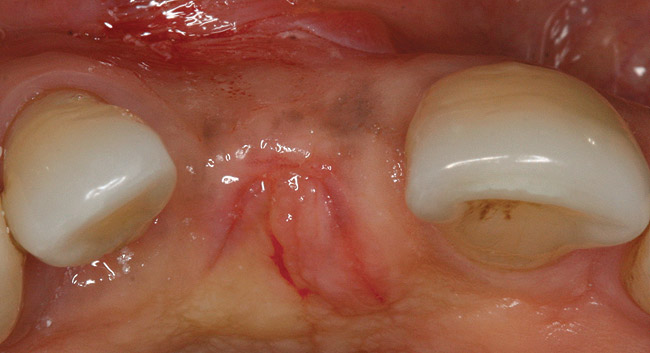

A 45-year-old woman presented with a narrow edentulous ridge in the maxilla (Figure 1). Following adequate anesthesia, a horizontal incision palatal to the crest and two vertical incisions were placed to outline the surgical field. A periodontal probe was used to measure the width of the alveolar crest at the most coronal dimension after a full-thickness flap was elevated (Figure 2). From the author’s experience, it was not necessary to maintain palatal bone-periosteum.

Figure 1  Patient missing maxillary right central incisor presents with ridge deficiency.

Figure 1